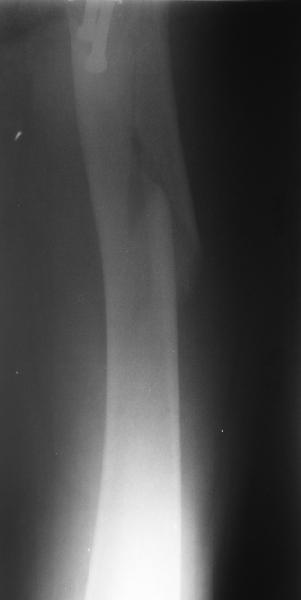

Еще одна боковая проекция. На сегодня назначен закрытый интрамедуллярный остеосинтез. Реконструкционного гвоздя для этой больной не нашлось, придется делать обычным.

Another lateral view. A closed nailing is scheduled for today. No reconstuction nail is available so a usual one is planned.